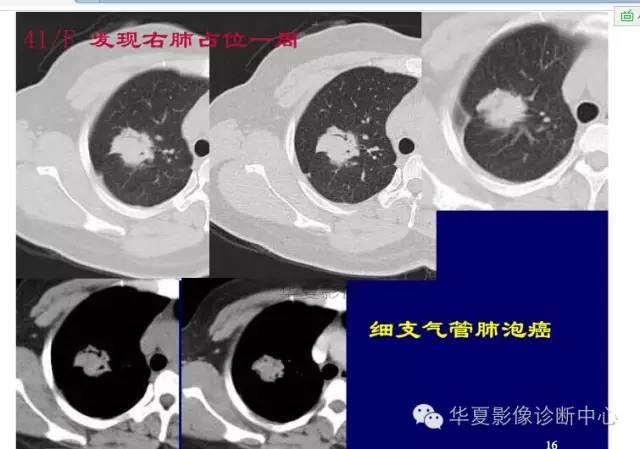

这一例是否GGO成分几乎没有

基本是实性的

那就按实性的分析

磨玻璃结节良恶性影像分析策略 都是支气管

胸膜凹陷,分叶征